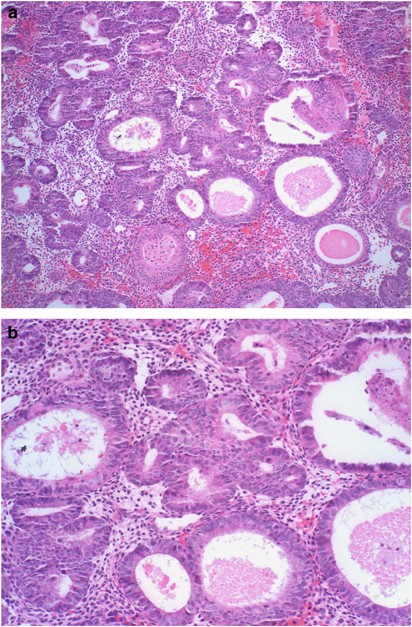

Figure 2

An example of adenocarcinoma in situ in case of complex atypical endometrial hyperplasia. (a) Lower power view (H&E, × 40). (b) The corresponding higher power (H&E, × 200).